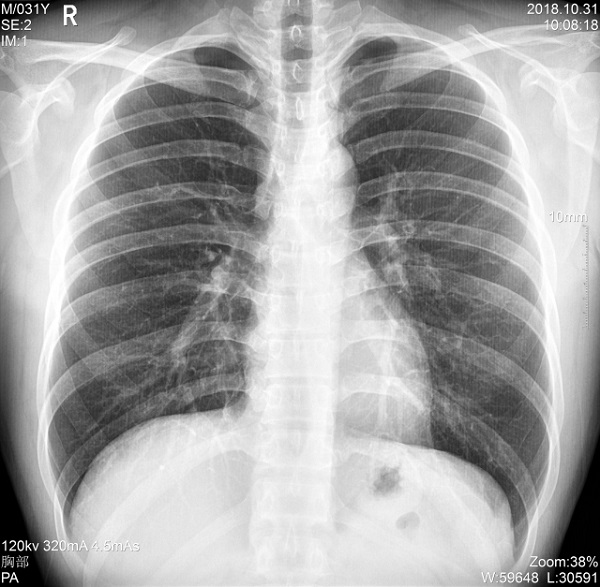

三、支持高千伏攝影 肺部紋理更有層次

PLX5500系列移動(dòng)DR的可調(diào)千伏達(dá)到150kV,在達(dá)到一定高電壓后,與骨骼相重疊的軟組織或骨骼本身的細(xì)小結(jié)構(gòu)及含氣的管腔等,均可清晰顯示。